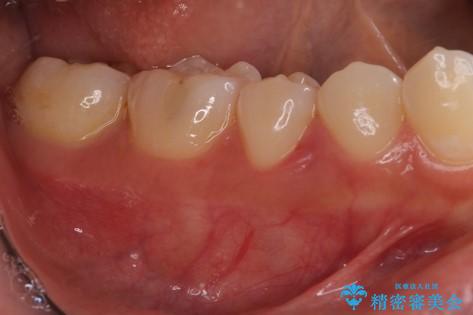

患者様は、他院で右下の歯を抜歯かもと言われました。全体の歯周病はなく、右下の1歯だけ骨が極端に減少していました(初診時歯周ポケット7mm。通常は3mm以下。)。その歯だけ咬合が強いことが原因と考えられたため、咬合を弱くする処置と減少した骨を再生する処置が必要になりました。